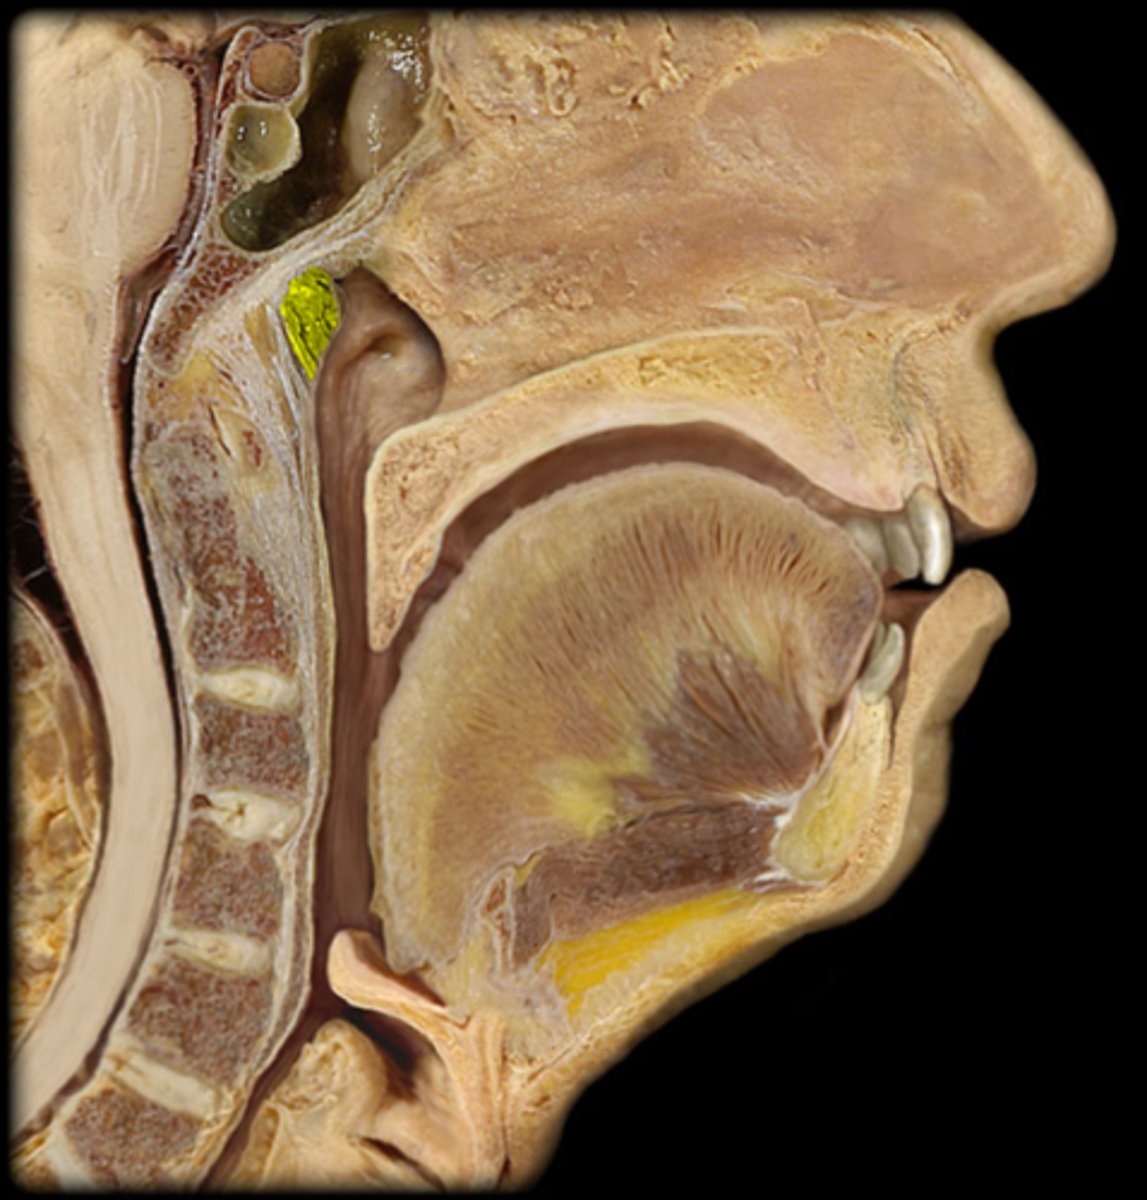

pharyngeal tonsil

1